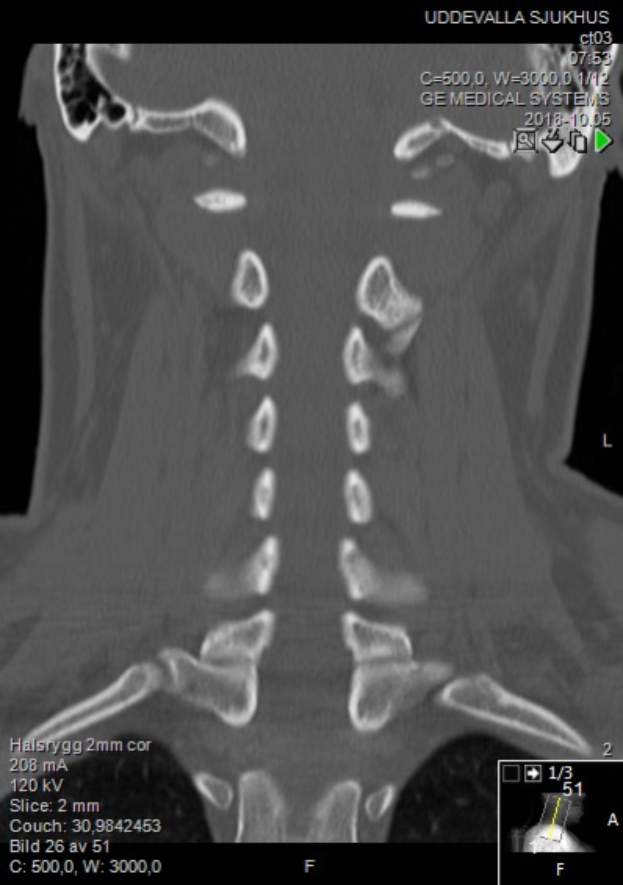

Eine MRT-Aufnahme des Halses eines Mannes, die einen Bruch zeigt, auf einem Computermonitor angezeigt.Branko Tlustek